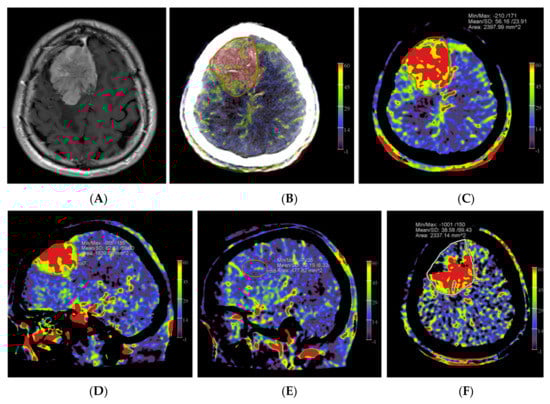

Our data clearly demonstrated a decline in rPBV when pre-embolization rPBV values were compared with post-embolization values. However, this effect was not significant but can most likely be explained by the low patient numbers included in this study. The calculated mean difference in rPBV of 3.33 with an SD of 2.04 corresponds to a large effect of size of 1.63. The power to find an effect of this size with a paired t-test on four observations is 60%, which illustrates that the observed effect is already of considerable size, even with such a small number of observations. This observation is in accordance with the findings of Wen et al. [21]. Interestingly, in patient no. 1, who showed the highest pre-embolization rPBV value with the largest ∆rPBV value, the highest amount of blood loss (500 mL) was reported. We noticed that embolized tumor portions appeared on the post-embolization perfusion images in two patterns, as hypoperfused and as blacked-out patterns, such as bone structures (Figure 4). Probably, the high density of stagnating contrast medium in embolized tumor regions resulted in a normalization issue in calculating the PBV maps, rendering these areas as bony structures on the PBV maps. The reason for the stagnation of the contrast medium might be the leakage of intravascular contrast into the meningioma, possibly facilitated by the embolization procedure. It is described in magnetic resonance perfusion imaging that meningiomas demonstrate typical time-intensity curves with a rapid signal drop during the first pass of contrast and slow signal return, indicating increased contrast leakage and permeability [24]. This phenomenon was not described in the few published papers about PBV imaging in hypervascular intracranial tumors. The presence of an intratumoral contrast medium after embolization might pose difficulties in calculating the post-embolization PBV scans. Next to a “blacked-out” phenomenon, this may lead to an overestimation of the PBV values on post-embolization scans. This might be a reason for the low ∆rPBV finding in patient no. 2. Future research should further clarify the impact of intratumoral contrast leakage on pre and post-embolization PBV imaging in the angiography suite.

Figure 4.

Pre- and post-embolization fill run and PBV mapping of a patient (no. 1) with a large right hemispheric meningioma. (A) Pre-embolization axial reformations of fill run and (B) whole brain PBV perfusion show dense, homogeneous, hypervascular enhancement of the tumor. (C) Post-embolization axial fill run reformation demonstrated tumoral areas with decreased enhancement and large areas with pooled contrast medium. (D) The corresponding axial whole brain PBV reformation shows both devascularized (arrows) and blacked-out (*) areas with pooled contrast medium.